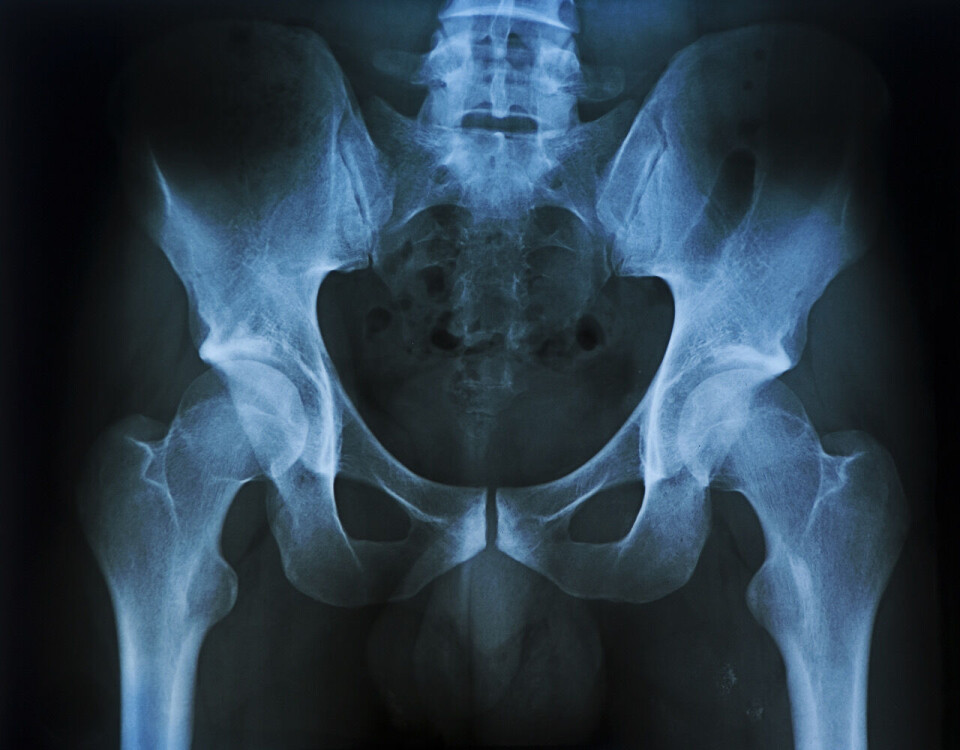

Tina åpner med en liten anatomileksjon:

– Tenk enkelt, gjør det enkelt. Det skal mye energi til for å knuse et bekken. Det er den sterkeste strukturen i kroppen, en ring som holder alt oppe.

Hun beskriver bekkenstrukturen med ring og vinger, organene i området: Kjønnsorganer, urinblære og tarmer, samt blodkarene, nervene og blodforsyningen til beina.

Ved skader så vil bukhinnene ikke lenger holde ting på plass.

– Alle nervene som kommer ut av ryggmargen kommer ut i bakre del av bekkenringen.

En bekkenskade kan påvirke mange organer, det er fare for både blødninger og organskader som kan gi komplikasjoner.